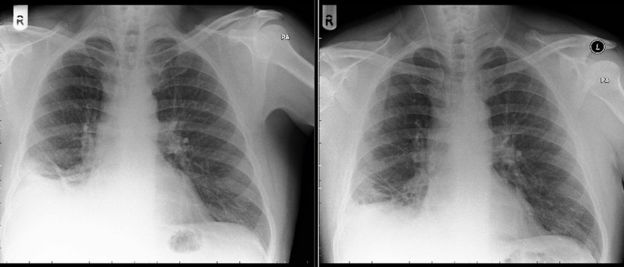

Dopo una radiografia che aveva mostrato la presenza di una massa in un polmone, i medici avevano diagnosticato all’uomo un cancro ai polmoni.

Durante la broncoscopia invece, i medici si sono accorti che nei polmoni dell’uomo era presente un cono di plastica giocattolo, che l’uomo aveva ricevuto in regalo al suo settimo compleanno. Il paziente dunque non era affatto malato di cancro.